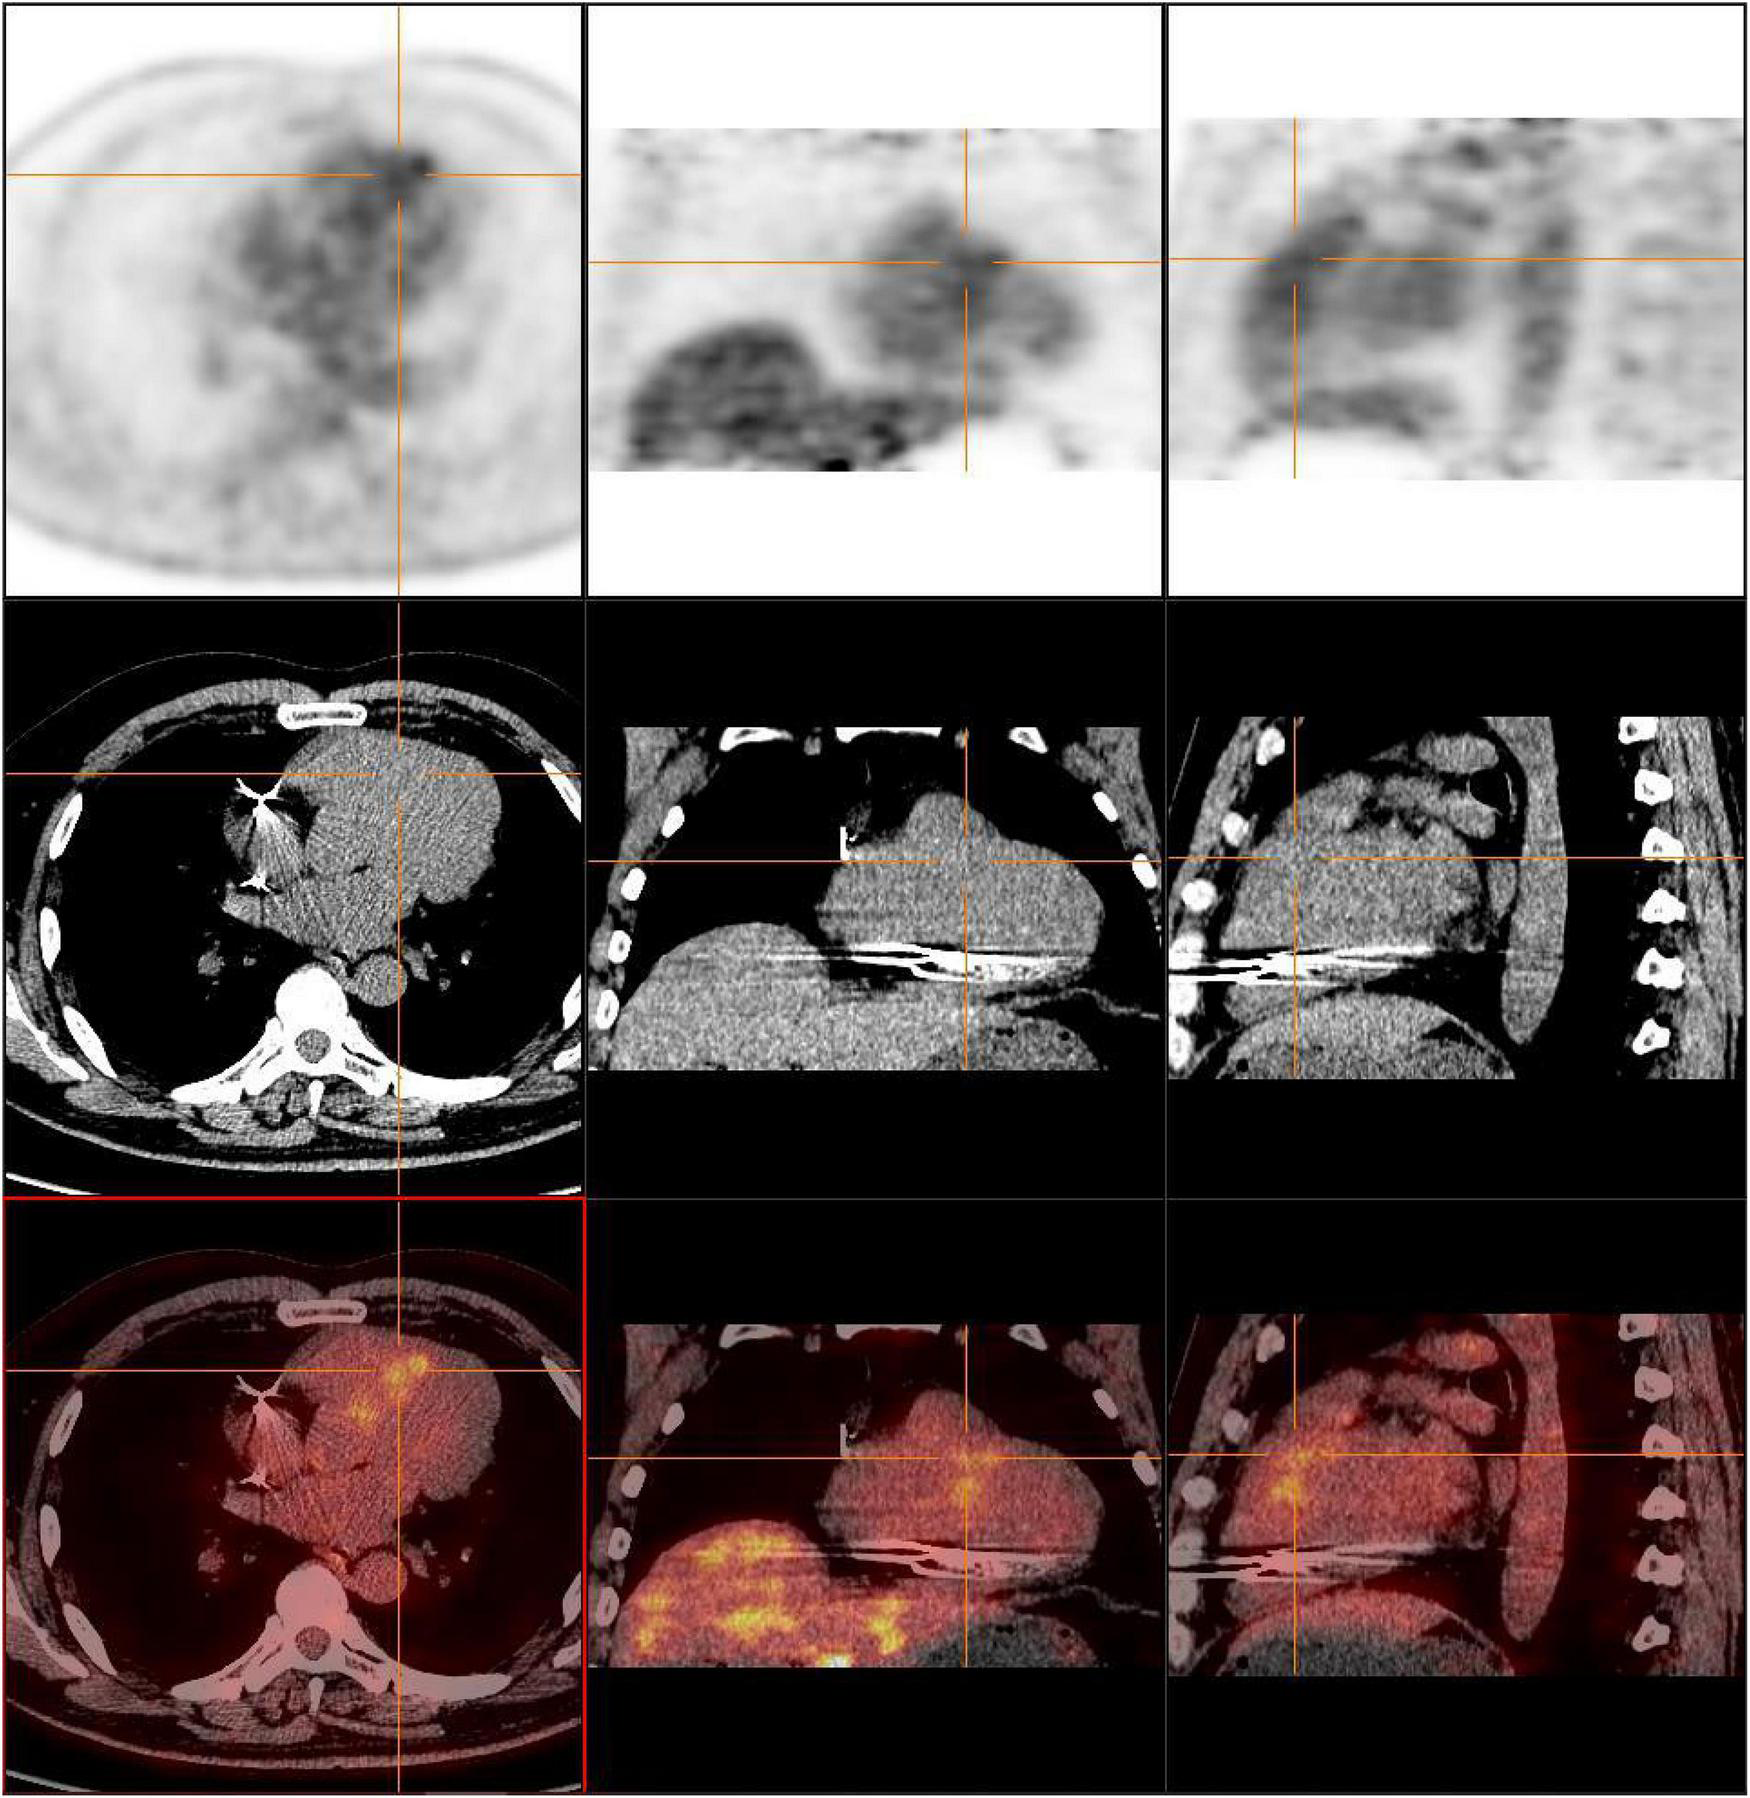

Surgery and medication did not improve the patient’s symptoms within the following 7 months. In local hospital repeat CMR imaging showed that LGE was aggravated (Figure 1). Fluorine-18 fluorodeoxyglucose positron emission tomography (FDG-PET) demonstrated intense multifocal cardiac uptake in the interventricular septum and right ventricle without abnormal lesions in other parts of the body (Figure 2). Adenosine technetium-99m (99mTc)-sestamibi myocardial perfusion imaging showed that blood perfusion was decreased in the middle and basal segments of the ventricular septum. The doctor considered that arrhythmia might be caused by cardiac tumor, and suggested that the patient should undergo cardiac biopsy in our hospital.

FIGURE 2

FDG-PET reveals intense multifocal cardiac uptake in the interventricular septum and right ventricle, and no abnormal lesions are found in other parts of the body. FDG-PET, Fluorine-18 fluorodeoxyglucose positron emission tomography.